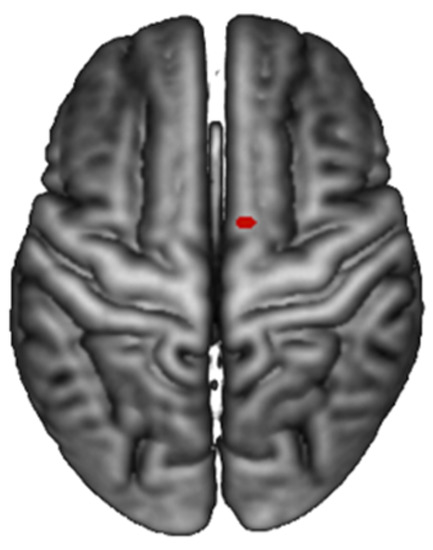

| Brain Region | Voxels | p-Value | Z | MNI Coordinates (mm) 10 |

|---|---|---|---|---|

| R Posterior-Medial Frontal (SMA) | 1 | 0.09 | 4.5 | 10 0 76 |